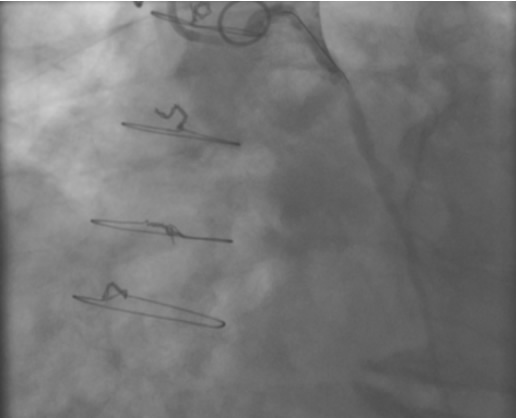

PCI of the vein and arterial grafts have unique challenges. For any PCI, guide support is very important for successful balloon and stent delivery. In a tortuous vein graft with a steep angle, advancement of a stent can be very difficult and challenging. Therefore, it is important to choose the best available catheter before starting PCI. Similar to the right coronary angiography, a JR4 guide catheter is most commonly used in this setting. However, Amplatz guide catheters for left vein grafts and multipurpose catheters for right vein grafts are better choices in certain anatomy. In Figure 8 and Figure 10 two examples of poor guide support in two vein graft interventions can be seen. Initially, a JR4 guide was used for PCI of the vein graft supplying the left anterior descending artery (LAD) without any success. However, after changing the guide to an Amplatz left 2 guide catheter, we achieved excellent support without any difficulty in advancing two stents (Figure 9). In Figure 10, difficulty is illustrated in engaging the vein graft ostium supplying the right coronary artery with a JR4 catheter. This vein graft has a very steep inferior take off from the aorta. After changing the guide to a multipurpose catheter, we were able to deliver three stents successfully without any difficulties (Figure 11). Similar challenges exist in the treatment of the left IMA or right IMA. These arterial grafts can be extremely tortuous making stent delivery very difficult. It may be necessary to use short length stents for a better deliverability or stents with lowest profile. Usually, similar to the native coronary intervention, a 6 French guide is appropriate for the routine use.

The most commonly used catheters for left heart catheterization and vein graft angiography can be seen in Figure 1 and Figure 4-13. Most of the vein grafts have horizontal take off and can be successfully engaged using a commonly used Judkins right number 4 (JR4) catheter. The JR4 catheter is the most commonly used catheter for the engagement of the right coronary ostium with horizontal take off. However, many vein grafts have unusual take off requiring different catheters. Many right coronary vein grafts have steep inferior take off making the ostial engagement with JR4 difficult or impossible (Figure 10). In such a scenario, a multipurpose catheter which has a shallow angulation is the best choice (Figure 11). The second major challenge in engaging vein graft ostia, particularly vein grafts supplying the left coronary arteries, is the shape of the aorta. A large aorta can make it very difficult for the JR4 catheter to reach the ostial vein grafts. In such a situation, Amplatz (AR) right and left (AL) catheters can be very helpful to reach the vein graft ostia. Amplatz catheters have a larger primary curve and have been used successfully in unusual superior take off of left coronary arteries or vein grafts and in large aorta. Amplatz catheters are available in different sizes (from smaller to larger curve: AR 1, AR2, AL2, AL2 and AL3). Occasionally, a very superior take off of a vein graft requires specially designed bypass graft catheters. Amplatz catheters are also extremely helpful in engaging native right coronary ostium with anterior take off.